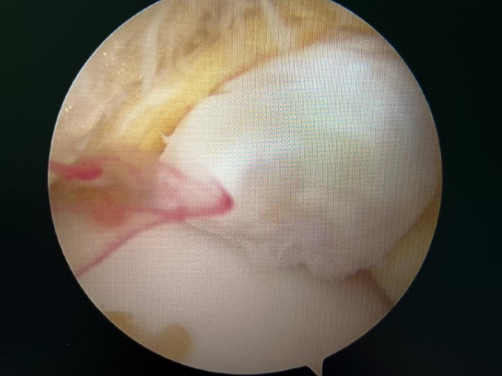

踝關(guān)節(jié)鏡見前方長(zhǎng)骨刺

醫(yī)生們?cè)谑中g(shù)中發(fā)現(xiàn),李先生的右踝關(guān)節(jié)軟骨損傷明顯,踝關(guān)節(jié)前方及內(nèi)外側(cè)均有不同程度的骨質(zhì)增生,相互撞擊引起疼痛,同時(shí)距腓前及跟腓韌帶斷裂。手術(shù)醫(yī)生利用磨鉆,小心翼翼將引起撞擊的骨刺一一去除,然后,修復(fù)了損傷的關(guān)節(jié)軟骨,最后,為他完成了距腓前和跟腓韌帶的修復(fù)。